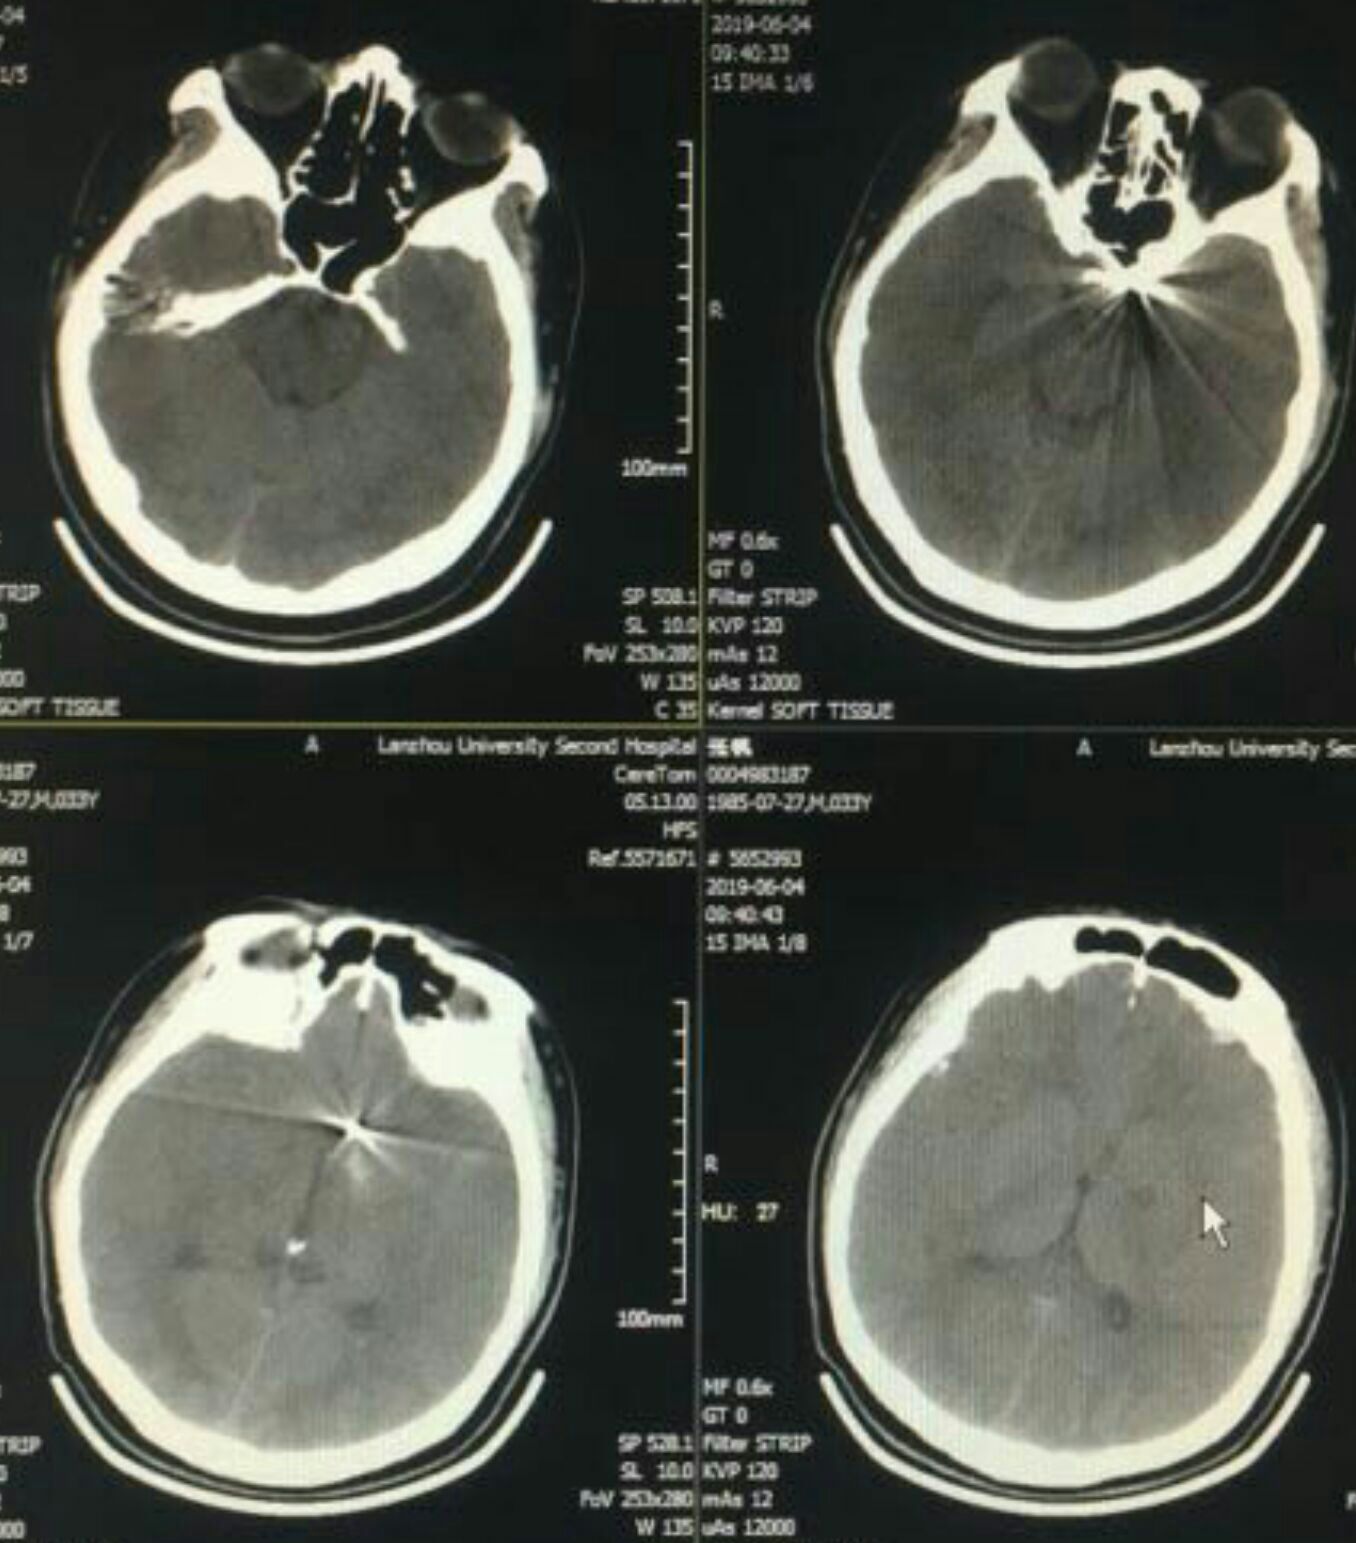

CT蛛网膜下腔出血

次日复查CT无出血,可见左侧内囊膝部小梗(缺血不到1小时啊!),真是后怕😣